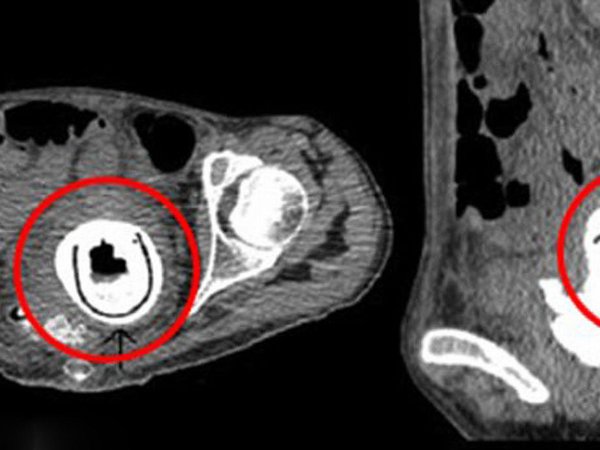

Sex toy ανακάλυψαν γιατροί σε νοσοκομείο της Βρετανίας, κάνοντας ακτινογραφίες σε 38χρονη γυναίκα. Το 12 εκατοστών sex toy βρισκόταν μέσα στο σώμα της για δέκα ολόκληρα χρόνια!

Το ερωτικό παιχνίδι, μήκους 12 εκατοστών, «αποκαλύφθηκε» όταν οι γιατροί υπέβαλαν τη γυναίκα σε μια σειρά από ακτινογραφίες, όταν εκείνη έσπευσε στο νοσοκομείο λέγοντας ότι αισθανόταν κουρασμένη, ότι υπέφερε από υπνηλία και συχνές ουρολοιμώξεις, και πως έχανε συνεχώς βάρος.

Η 38χρονη, το όνομα της οποίας δεν έχει γίνει γνωστό, έπασχε από κυστεοκολπικό συρίγγιο, μια πάθηση του ουροποιητικού συστήματος, ενώ σύμφωνα με τους γιατρούς, αν το παιχνίδι έμενε μερικά ακόμη χρόνια μέσα της, θα μπορούσε να αποβεί μοιραίο για εκείνη, οδηγώντας τη στον θάνατο.

Οι γιατροί αφαίρεσαν το sex toy από τη γυναίκα, ενώ η ίδια έχει σήμερα αναρρώσει πλήρως, ωστόσο δεν μπορεί να πιστέψει ότι η αιτία για την ταλαιπωρία που είχε με την υγεία της όλα αυτά τα χρόνια ήταν ένα ερωτικό παιχνίδι.